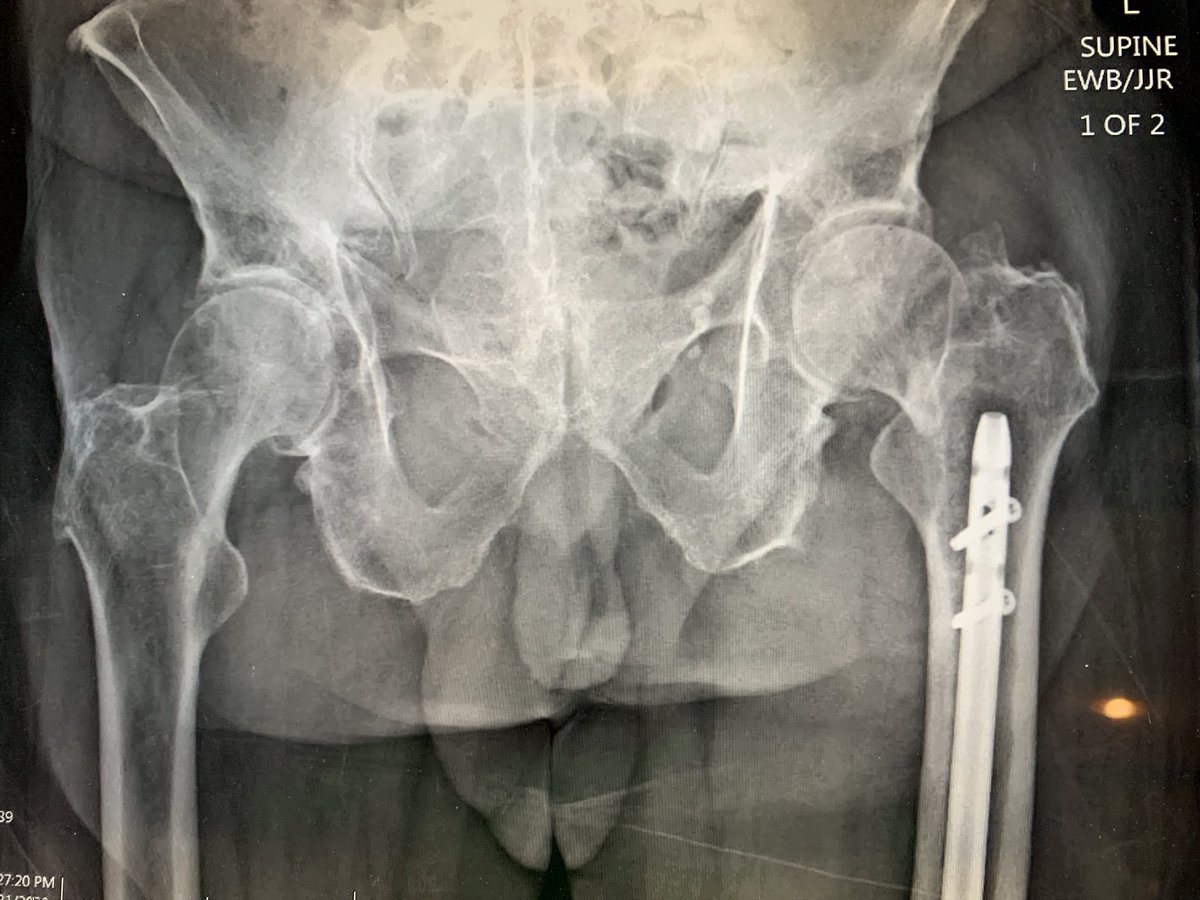

I was called: concerns were acetabular fracture, high dislocation risk, management of femur fracture, concerns for femoral rotation.

We used a revision style cup that allowed for locking screws to treat acetabular fracture.

DM to mitigate higher dislocation concerns.

We discussed hemi but concern over protrusio